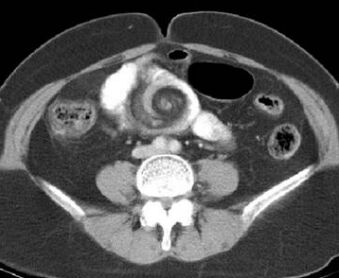

74.病人主訴腹脹、反胃及腹部悶痛;腹部電腦斷層檢查呈現如附圖。下列何項初診斷最恰當? (A)volvulus (B)intussusception (C)parasite infection (D)acute appendicitis